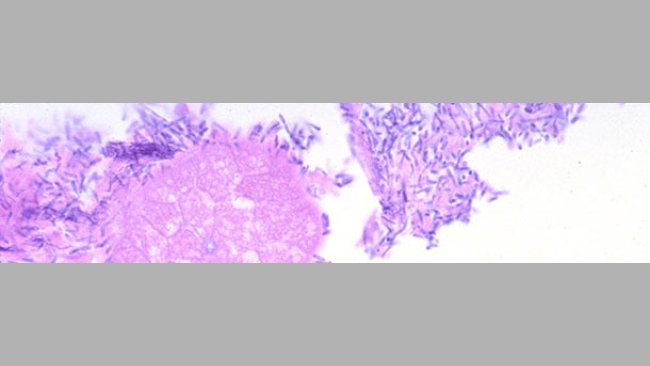

La muestra ideal para el diagnóstico de patógenos entéricos neonatales es el envío de lechones vivos.